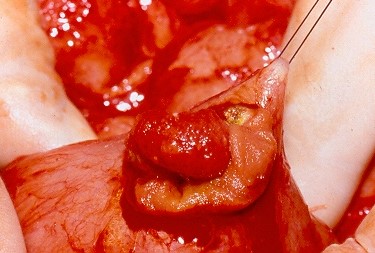

Μακροσκοπική εικόνα δεξιού εξαρτήματος – Καλοήθες νεόπλασμα Brenner (Ευγενική παραχώρηση Dr. V. Penopoulos)